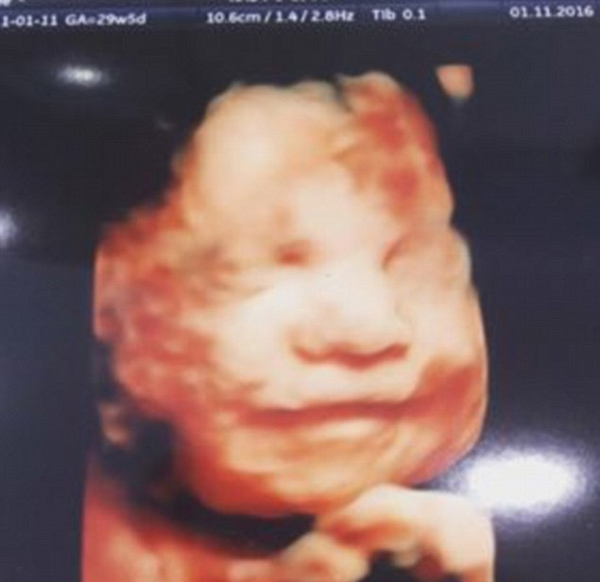

据英国《每日邮报》11月3日报道,27岁的英国孕妇艾梅·费根(Aimee Fagan)(已育有两个女儿)2日在利物浦的超声检查中心接受4D孕检,当她3岁的小女儿对她腹中的胎儿说话时,胎儿竟露出了微笑。

艾梅当天在家人的陪伴下接受了4D孕检,目前她已怀孕30周。她说,在扫描期间,每当她3岁的小女儿莫莉对着她隆起的腹部说话时,腹中的胎儿就会微笑,而当莫丽停止说话时,胎儿也停止了微笑,仿佛婴儿知道莫丽是她姐姐。对此,艾梅和超声技师都感到非常惊讶。

过去,人们以为胎儿在出生后通过模仿自己的妈妈才学会微笑,但现在一些专家认为,子宫中的胎儿也有面部表情。